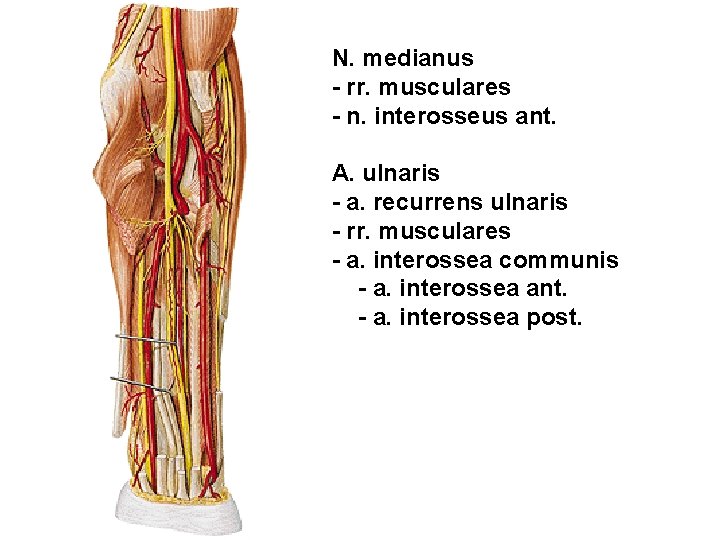

N. medianus - rr. musculares - n. interosseus ant. A. ulnaris - a. recurrens ulnaris - rr. musculares - a. interossea communis - a. interossea ant. - a. interossea post.